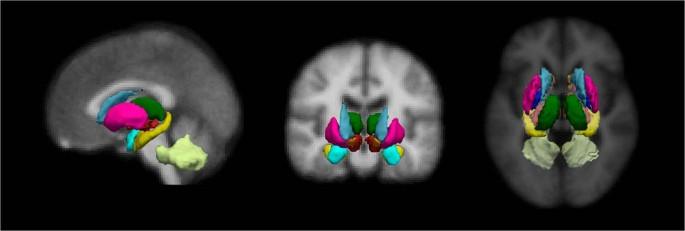

Ατροφία εγκεφάλου με νόσο Πάρκινσον